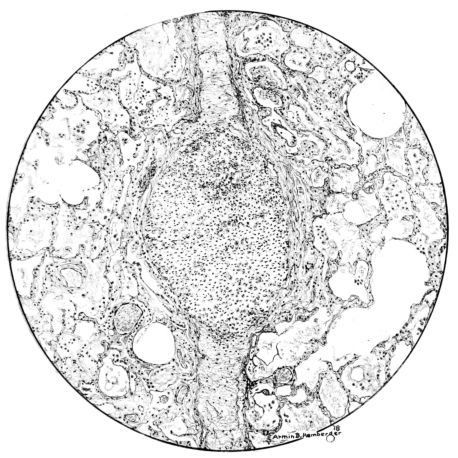

FIG. I. AUTOPSY NO. 99. ACUTE HEMORRHAGIC AND ULCERATIVE LARYNGOTRACHEITIS.

FIG. II. AUTOPSY NO. 98. DRAWING OF A SECTION THROUGH A TRACHEA SHOWING NECROTIZING HEMORRHAGIC INFLAMMATORY PROCESS OF THE MUCOSA.

Early in the disease the congestion and the hemorrhages that have been described in the mucous membrane of the nasopharynx (14 and 94) are also conspicuous features in the lining of the trachea and bronchi (Fig. I). This membrane is swollen, turgid, red, and covered by a copious, mucous exudate which may be clear, but much more frequently is blood-stained or opaque and yellowish in color. The blood, variable in amount, may be fresh and red; and after the mucous exudate on the surface is removed, more intense red foci stand out on the congested base (47, 90, 157). Frequently, as the bronchi are approached, the red color of the mucosa becomes more intense and may have a garnet tinge. Membranes such as are encountered in the more usual necrotizing inflammatory processes, like diphtheria, have not occurred in the trachea and larger bronchi in this series (108, 128, 157).[3] The exudate peels off readily, and as indicated above, leaves a velvety red surface, 14dotted here and there with darker or more intensely red foci. Small ulcerations of the mucosa occur, but are inconspicuous (82, 156). As the finer ramifications of the bronchi are approached, the accumulation of the exudate in their lumina becomes more and more marked, and on cross section of the lung, they often stand out conspicuously on account of their increased size and projecting, seromucous, blood-stained content (101, 149, 162).

The changes are less marked, perhaps, in the trachea than in its finer ramifications. The mucosa is constantly more or less destroyed and large areas, usually focal, are entirely devoid of their epithelial covering. This is replaced by a sparse exudate, composed largely of red blood cells, mucus, a small amount of fibrin, and nuclear fragments (Fig. II). It may dip into the submucosa for a short distance, but usually these indentures are associated with the ducts of the mucous glands into which the inflammatory reaction extends. A more striking feature than the exudate, however, is the edema and the congestion of the submucosa. The loose areolar tissue of the submucosa is spread widely apart, and throughout it distended blood vessels are very conspicuous. Occasionally such a vessel is broken and actual hemorrhage appears in the submucosa. Occasionally, too, the inflammation extends down the duct to the mucous gland itself, and here, also, aplastic inflammatory reaction is evident, inasmuch as the acini now stain intensely red with the cells undifferentiated from each other and specked here and there by broken remains of the dead nuclei (Fig. III). After the disease has continued for a short period, even at the end of five or six days, some regeneration of the epithelial lining may be seen (3) (Fig. IV). But despite this, the acute picture persists, and there goes on, side by side, an attempted repair characterized by epithelial regeneration and the same evidence of acute change. Since the lesion is essentially a superficial one, scars or contractures of any extent are not encountered in the trachea, even in examples of the disease that have ended fatally only after many weeks.[4]